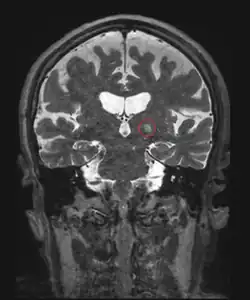

HIFU is combined with other imaging techniques such as medical ultrasound or MRI to enable guidance of the treatment and monitoring.

HIFU therapy requires careful monitoring and so it is usually performed in conjunction with other imaging techniques.

Pre-operative imaging, for instance CT and MRI, are used to identify general parameters of the target anatomy. Real-time imaging provides safe and accurate noninvasive targeting and monitoring. Both MRI and medical ultrasound have been used. These techniques are known respectively as Magnetic Resonance guided Focused Ultrasound Surgery (MRgFUS)[32][33] and Ultrasound guided Focused Ultrasound Surgery (USgFUS) respectively.[1][34]

MRgFUS is a 3D imaging technique. It features high soft tissue contrast and provides information about temperature, thus allowing ablation to be monitored. However, low frame rates make this technique perform poorly in real-time imaging while high costs limit its use.[35]